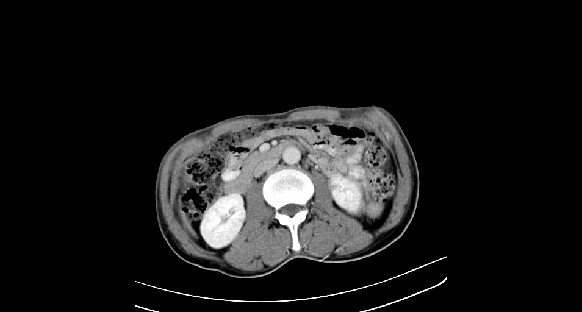

男性,70岁,体检b超发现左肾占位,请各位战友发表一下观点

左肾有两个病灶,且较大的病灶内可见点状钙化灶,增强扫描边缘也是呈渐进性强化,中央部分未见明显强化